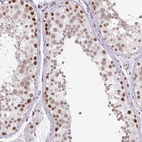

Immunohistochemical staining of human skin shows strong nuclear positivity in squamous epithelial cells.